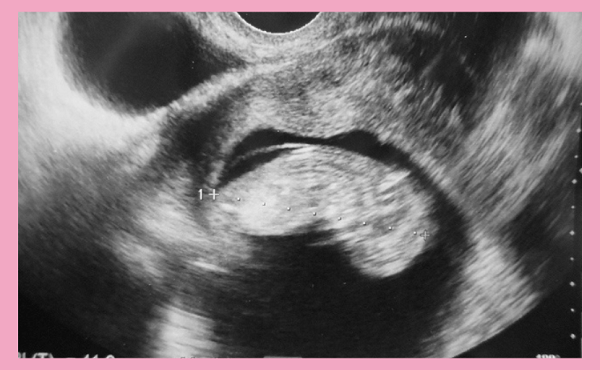

妊娠11週目のエコー写真です。